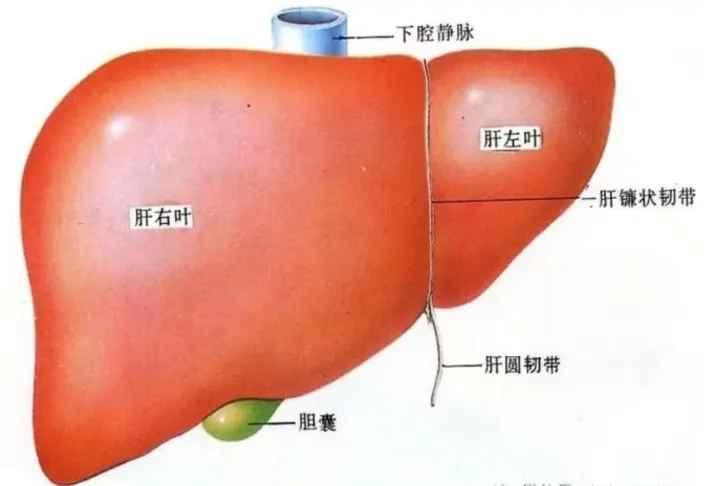

肝脏超声解剖

肝脏是人体非常重要的一个部位,肝脏部位一旦出现异常时,需要快速进行扫查确定具体的位置进行相应的治疗,超声检查是发现肝脏局灶性如肝囊肿、肝脓肿、肝血管瘤、肝局灶性结节增生、原发性肝癌、转移性肝癌、肝包虫病等病变的重要手段,了解肝脏的解剖结构也是必不可少的,肝脏的解剖没有想象中的那么难,我们可以按下面方式来展开进行了解:即......